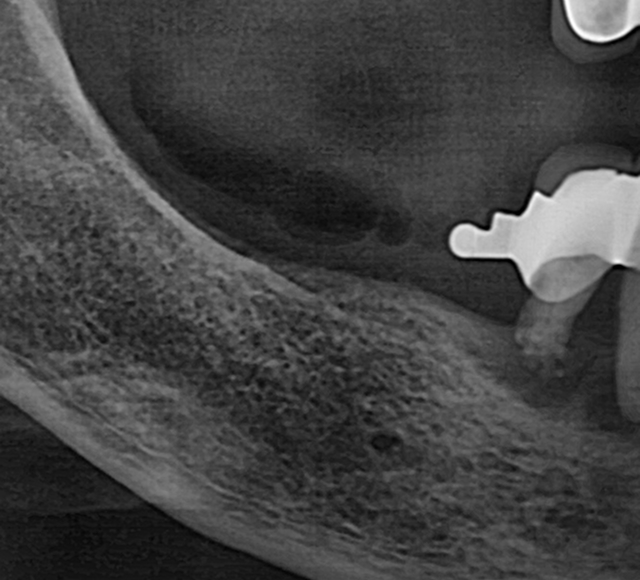

고난도 뼈이식 케이스

- 정밀 영상 진단으로 결손 부위를 파악하여 안전하게 골이식

- 미세 수술 장비를 활용해 식립 안정성 및 성공률 향상